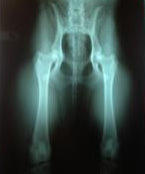

~ Z U C H T Z I E L ~ Eine Zucht zu haben, bringt viel Verantwortung mit sich. Freud und Leid liegen nah beieinander. Jedoch haben wir uns nach langem Überlegen entschieden diesen Schritt zu wagen. Unsere Zucht basiert auf VIER Säulen: All das versuchen wir in unserer Zucht zu vereinen! Der Hund soll dem Rassestandart des Retrievers entsprechen, von der Gesundheit bis hin zu den wesentlichen Arbeitsanlagen. Man darf eben nicht vergessen wozu der Golden und Labrador Retriever gezüchtet wurden: sie sind und bleiben Apportier- und Jagdhunde. Ansonst wäre der Retriever nicht der, den wir alle kennen und lieben. Da wir unter den strengen Auflagen des ÖRC (Österreichischen Retrieverclub) züchten, werden ausschließlich Hunde zur Zucht eingesetzt, die diesen Anforderungen auch entsprechen - sowohl gesundheits-, also auch wesenstechnisch. Das gilt natürlich auch für die sorgfältige Auswahl des jeweiligen Deckpartners. Was wir leider nicht abgeben können ist eine Garantie auf die gesundheitliche Entwicklung der Welpen. Wir können nur versichern nach bestem Wissen und Gewissen gehandelt / verpaart zu haben. Zur Aufrechterhaltung der Qualität unserer Zucht benötigen wir Rückmeldungen von unseren Welpenkäufern. Wir erwarten daher von ihnen, dass sie ihre Lieblinge zwischen dem ersten und zweiten Lebensjahr auf HD / ED / OCD (Hüfte / Ellbogen / Schulter) röntgen lassen. Des Weiteren soll nach Vollendung des 1. Lebensjahres eine augenärztliche Untersuchung bei einem zertifizierten ECVO Arzt durchführt werden. Warum ist das so wichtig? Daraus ergibt sich das für uns zuchttechnisch so wichtige Feedback! Gibt die Hündin ihre Gene gut weiter ? - War es die richtige Kombination der Elterntiere? usw. An dieser Stelle ein großes DANKESCHÖN an all unsere Welpenkäufer die ihrer Verpflichtung bereits nachgekommen sind. <3